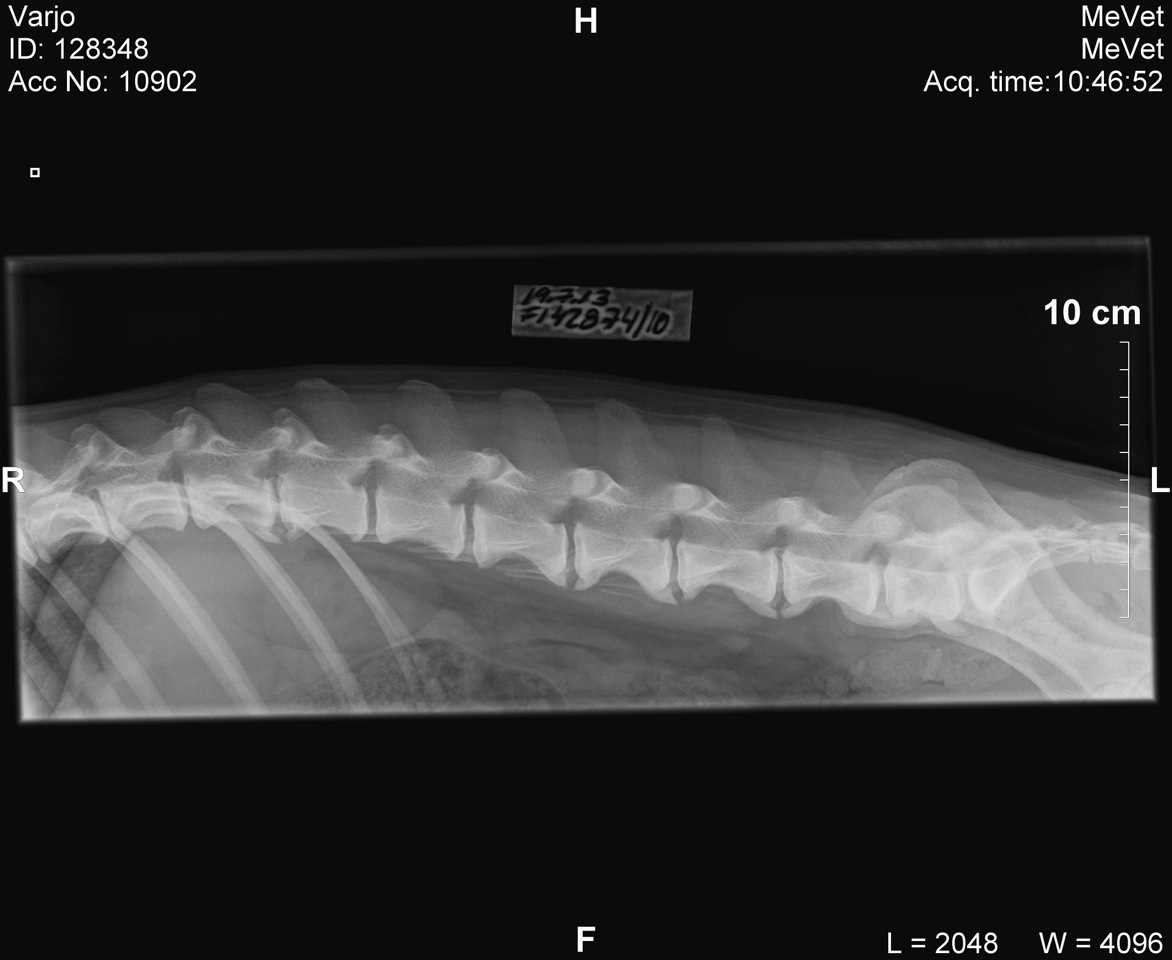

Viralliset selkäkuvat

Välimuotoinen lanne-ristinikama: LTV0 (normaali)

Selän spondyloosi: SP3 (aste 3, keskivaikea)

(7/13)

rintaranka,

lanneranka

Qisa viety eläinlääkäriin 19.7.13, koska se kiljahtaa syliin nostettaessa (ei kiljahda, jos hyppä itse).

Lisäksi toisten koirien kanssa leikkiessä suuttuu, mikäli sen takapäähän osutaan. Oireilu kestänyt keväästä saakka.

Eläinlääketieteen kandidaatti Elise Luttinen:"Ei selkeää ontumaa. Takajalkojen liikkeet hieman laiskat,

ei ojenna takajalkoja kunnolla. Palpoidessa reagoi lievästi rinta-lannerangan liitosalueen paineluun.

Oikeaa lonkkaa ulospäin taivutettaessa reagoi, murahtaa."

Diagnoosi:"Selässä runsaasti spondyloosimuutoksia. Lannenikamia 7 kpl. L6-L7 välissä kiinni kasvanut

spondyloosisilloittuma, näkee sekä ventraalisesti että lateraalisesti. L3-L4, L4-L5 ja L5-L6 väleissä

kiinni kasvamassa olevat silloittumat. Jokaisessa lannenikamassa spondyloosimuutoksia. Myös rintarangan

alkuosassa nikamissa pieniä luupiikkejä. Varjon oireilu johtuu todennäköisesti spondyloosimuutoksista.

Liikunta ja harrastaminen Varjon voinnin mukaan."